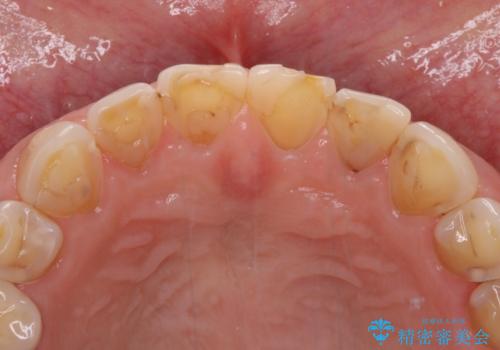

- 咬み合わせと度重なる応急処置の繰り返しにより、前歯がガタガタになってしまったとのことで来院された患者様です。

4本の前歯が気になっていたので、全てをオールセラミッククラウンにて補綴治療を行うこととしました。

4本とも治療前の歯髄の状態は正常でしたが、補綴治療により歯を大きく削ることになるため、歯髄が炎症を起こすリスクがあることを了解いただきました。